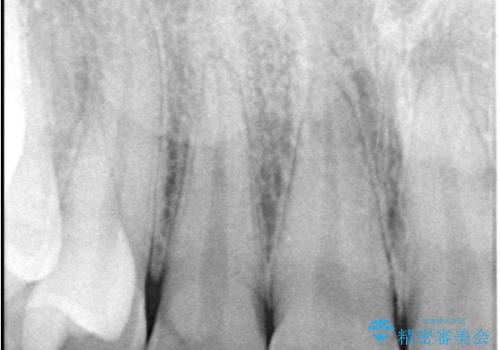

- 主訴:右上の前歯が何しなくても痛い

右上2番の歯に自発痛を認め、症状や歯髄診・レントゲン像から不可逆性歯髄炎と診断し、精密根管治療から歯冠補綴まで行うこととなりました。

初診時に歯髄診断を行い、不可逆性歯髄炎と診断し抜髄から補綴修復までの流れを説明し、精密根管治療、ファイバ-コア築造、オールセラミッククラウン(St)修復を行うこととしました。